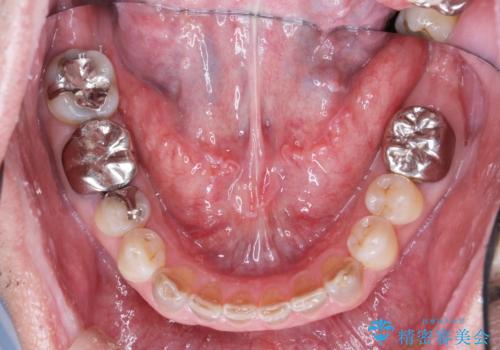

- 他院で上顎は全て抜歯し、入れ歯にする必要があると言われ相談に来院されました。

検査の結果、重度の歯周病であることから保存が難しい歯は抜歯を行いインプラントを、残すことが可能な歯には再生治療を含めた歯周病治療を行いより多くの歯を残す歯周病治療を計画します。